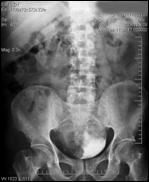

4.1. Radiografia renovezicala simpla si UIV raman examenele de baza pentru diagnosticul etiologic al oricarui pacient cu hematurie. Tumorile vezicale au drept semn radiologic cardinal imaginea lacunara pe cistograma urografica. Tumorile infiltrative pot induce modificari ale supletii peretelui vezical, care devine rigid, inextensibil, retractat etc. in zonele patologice. Ureterohidronefroza sau rinichiul mut sunt rezultatele invaziei si obstructiei ureterelor intramurale induse de tumorile solide, infiltrative (Fig.27,28,29).

Figura 28. Imagine

lacunara de 2,8/2 cm, in aria vezicii urinare, sugerand tumora

vezicala.